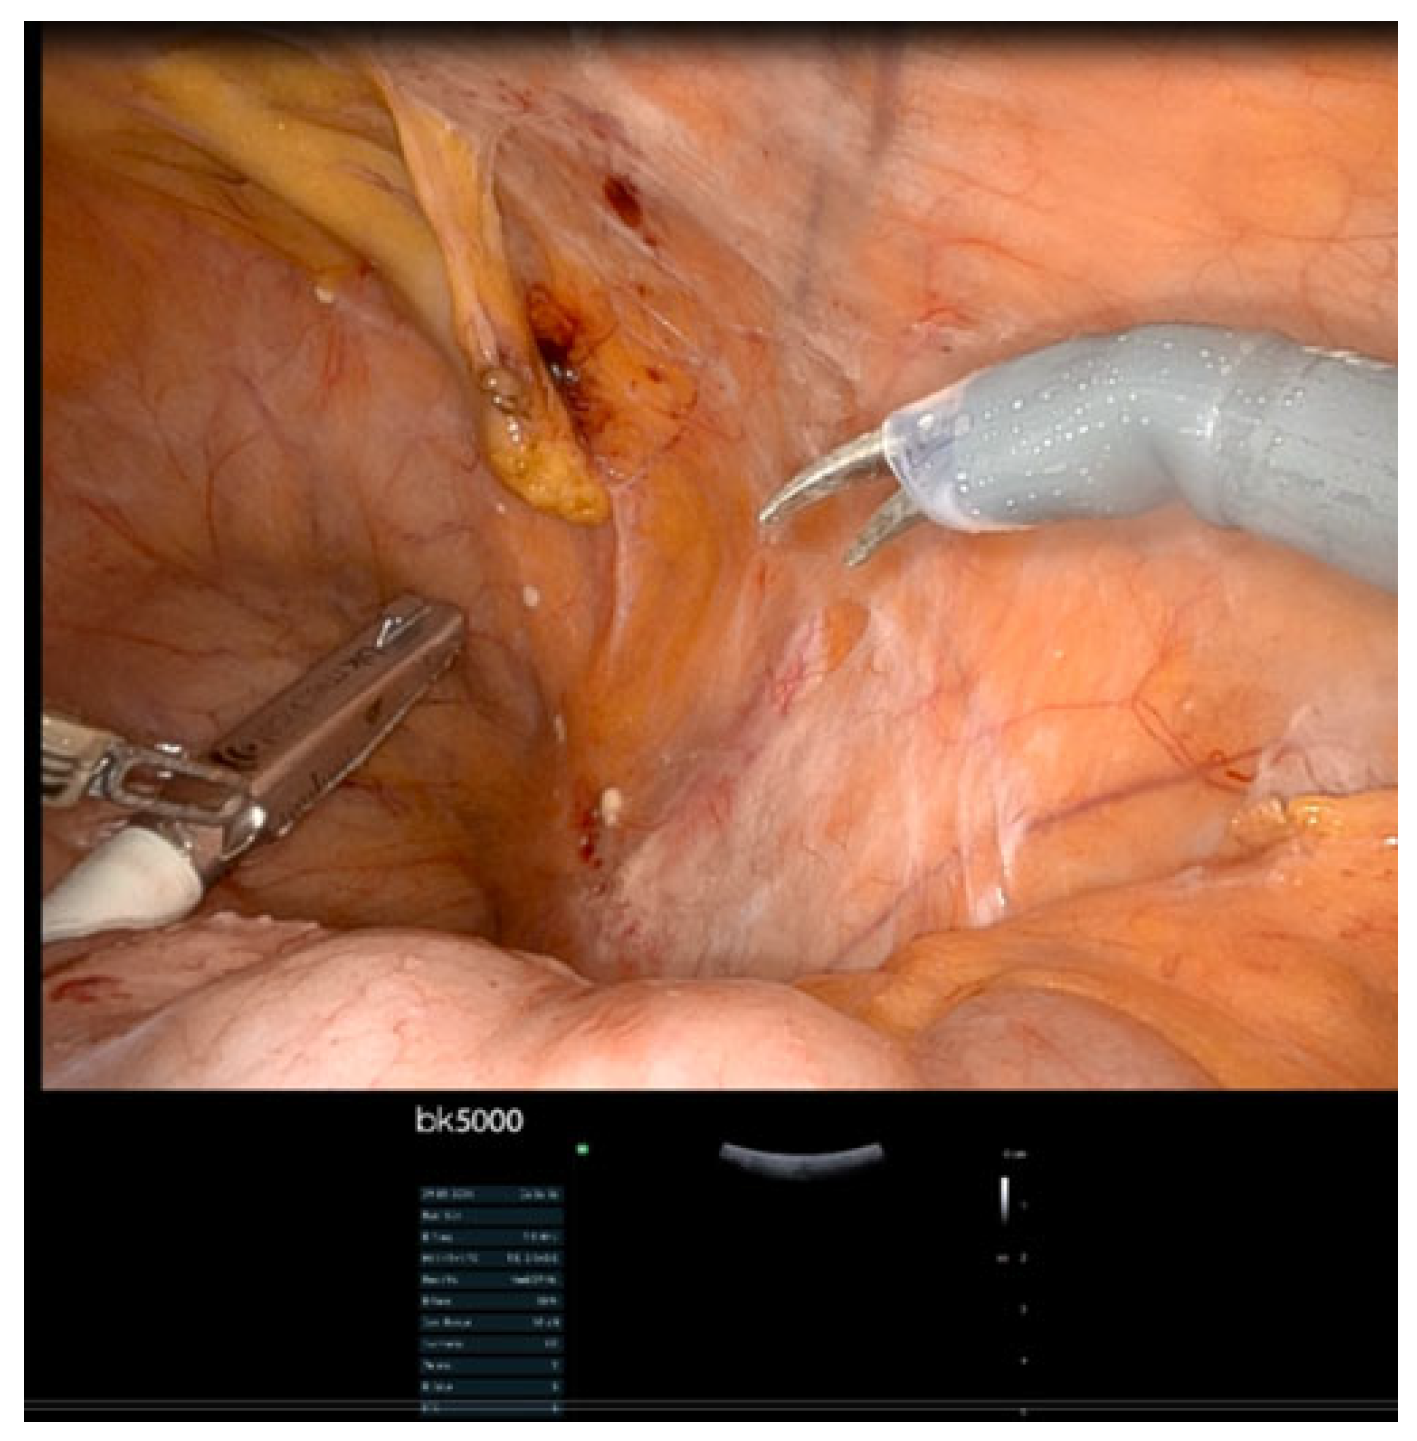

- IOUS in gynecological oncology lymph node assessment and staging

- Real-time confirmation of suspicious nodes before excision

- Precise needle guidance for targeted biopsy

- Immediate assessment of resection completeness

- Identification of critical vascular relationships to prevent injury